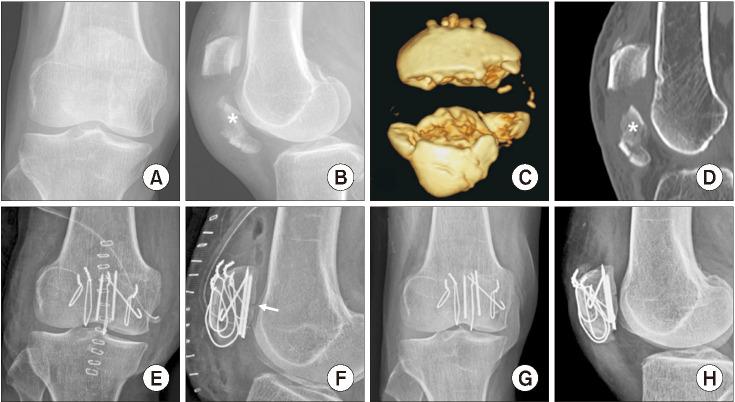

Treatment of comminuted patellar fractures accompanied by coronal split articular and inferior pole fragments is a challenge. To treat this difficult fracture, we perform articular fragment detachment and separate fixation for coronal split articular and inferior pole fragments. We aimed to evaluate the radiological and clinical outcomes of our technique in comminuted patellar fractures at least 1 year after surgery.

Between January 2019 and June 2022, 15 patients diagnosed with comminuted patellar fractures accompanied by coronal split articular and inferior pole fragments based on preoperative computed tomography underwent surgery using the articular detachment technique. The key point of this technique was anatomical reduction and subchondral fixation of the coronal split articular fragment to the superior main fragment after complete detachment of the coronal split fragment from the inferior pole. The remaining inferior pole was fixed using a separate construct. Postoperative articular gap, articular step-off, and complications, including resorption, reduction loss, and avascular necrosis of fixed articular fragments, were evaluated as radiological outcomes. Range of motion and the Lysholm scores were used to evaluate clinical outcomes.

Among the 15 patients, the coronal split articular fragments were fixed using Kirschner wires in 13 patients and headless screws in 2 patients. The inferior poles were fixed using separate vertical wiring in 13 patients and tension-band wiring in 2 patients. A postoperative articular gap was noted in 7 patients, with an average articular gap of 1.0 mm (range, 0.7-1.6 mm). No articular step-off was observed. Bone union and normal range of motion were achieved in all patients. On the 1-year postoperative lateral radiograph, resorption of the articular fracture site was seen in 5 patients. There was no loss of reduction or avascular necrosis of the coronal split articular fragments. The average postoperative Lysholm score at 1 year was 89.3 ± 4.1 (range, 82-95).

治疗伴有冠状面关节分裂和髌骨下极碎片的粉碎性髌骨骨折是一个挑战。为了治疗这种复杂的骨折,我们对冠状面关节分裂和髌骨下极碎片进行关节片游离和单独固定。我们旨在评估我们的技术在术后至少 1 年治疗粉碎性髌骨骨折的放射学和临床结果。

2019 年 1 月至 2022 年 6 月,根据术前 CT 诊断为伴有冠状面关节分裂和髌骨下极碎片的粉碎性髌骨骨折的 15 例患者采用关节游离技术进行手术。该技术的关键是在完全游离冠状面关节片与髌骨下极后,对冠状面关节片进行解剖复位和软骨下固定至主要上髌骨片。剩余的髌骨下极采用单独的固定方式。术后关节间隙、关节台阶和并发症(包括吸收、复位丢失和固定关节片的缺血性坏死)被评估为放射学结果。关节活动度和 Lysholm 评分用于评估临床结果。

在 15 例患者中,13 例采用克氏针固定冠状面关节片,2 例采用无头螺钉固定。13 例采用单独的垂直布线固定髌骨下极,2 例采用张力带布线固定。7 例患者术后出现关节间隙,平均关节间隙为 1.0mm(范围为 0.7-1.6mm)。未观察到关节台阶。所有患者均获得骨愈合和正常的关节活动度。在术后 1 年的侧位 X 线片上,5 例患者可见关节骨折部位吸收。冠状面关节片无复位丢失或缺血性坏死。术后 1 年平均 Lysholm 评分为 89.3±4.1(范围为 82-95)。